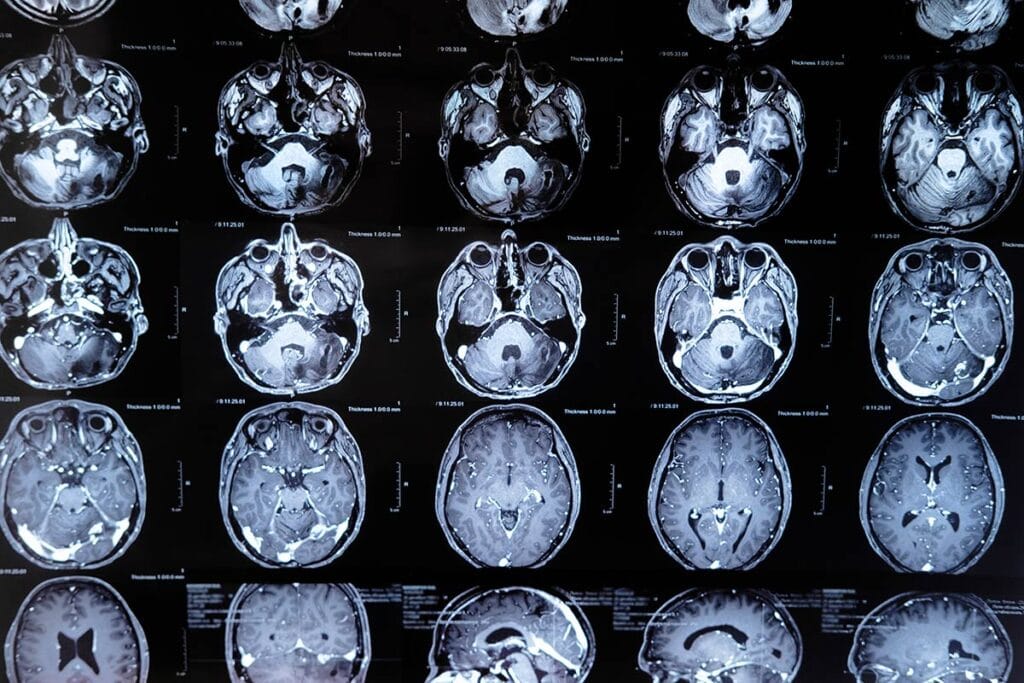

Research shows that for every fatal overdose, there are an estimated 15 to 20 non-fatal overdoses. In Canada, this translates to staggering numbers—while 44,000 people have died from fatal overdoses since 2016, more than 650,000 non-fatal overdoses have occurred. These incidents are often accompanied by severe, sometimes irreversible, injuries, with brain damage being one of the most concerning outcomes. During an overdose, breathing becomes shallow or may stop entirely, cutting off oxygen to the brain. Neurons, which rely on oxygen to function, can be permanently damaged in just a few minutes, resulting in hypoxic brain injuries.

Hypoxic brain injury, caused by a lack of oxygen during an overdose, has severe consequences. People who survive an overdose may experience cognitive impairments, including memory loss, difficulty with attention and decision-making, and even motor coordination issues. These deficits make it exceedingly challenging for survivors, particularly those already grappling with substance use disorders, to manage their daily lives or pursue recovery. As many frontline workers have observed, non-fatal overdoses often lead to significant neurological damage that complicates addiction treatment.

Studies from British Columbia in 2023, which analyzed health data from 824,000 people, found that individuals who experienced an overdose were 15 times more likely to have also sustained a hypoxic brain injury. These injuries may not always be immediately apparent, and in many cases, survivors of overdoses do not receive proper neurological assessments. Another federal study from 2019 to 2020, which looked at over 4,000 opioid-related hospitalizations, found that 4.2% of those admitted for drug overdoses were also diagnosed with hypoxic brain injuries. However, experts believe this figure underestimates the true extent of the problem, as many overdose victims do not seek hospital care or are not evaluated for brain damage.

The potential effects of these injuries are profound. Survivors may suffer from emotional dysregulation, cognitive delays, and impaired problem-solving abilities—issues that significantly hinder their ability to manage addiction and participate in rehabilitation programs. One particularly troubling condition linked to opioid overdoses is an amnestic syndrome, which affects the hippocampus, the part of the brain responsible for memory. This syndrome, along with other cognitive deficits like reduced verbal fluency and processing speed, has made recovery more difficult for people with opioid use disorder (OUD).